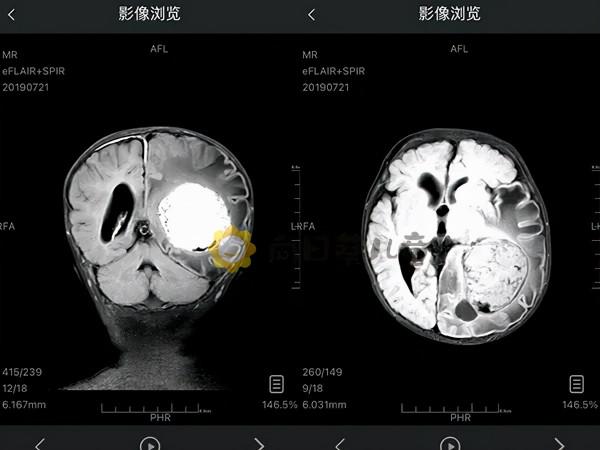

很快,涵涵被確診為脈絡叢乳頭狀瘤,這是腦瘤的一種。

脈絡叢腫瘤是起源於室內脈絡叢上皮細胞的腫瘤,好發於兒童,是1歲時最常見的腦腫瘤。

脈絡叢腫瘤可以分為良性和惡性。脈絡叢乳頭狀瘤為良性,脈絡叢癌為惡性,脈絡叢乳頭狀瘤與脈絡叢癌的比例為5:1。

脈絡叢乳頭狀瘤生長緩慢,外科手術可以治癒。脈絡叢癌顯示惡性特徵,生長迅速,常瀰漫侵及腫瘤周圍腦組織,常見腦脊液擴散,並轉移到其他正常腦部和脊髓組織。

醫生將腫瘤的照片給他們看,全家人都非常驚訝,怎麼有這麼大的東西在他小小的腦袋裡,就跟鵝蛋一樣大。醫生說,我們已經把能看到的全部切掉了,後期就靠涵涵自己去闖關了。